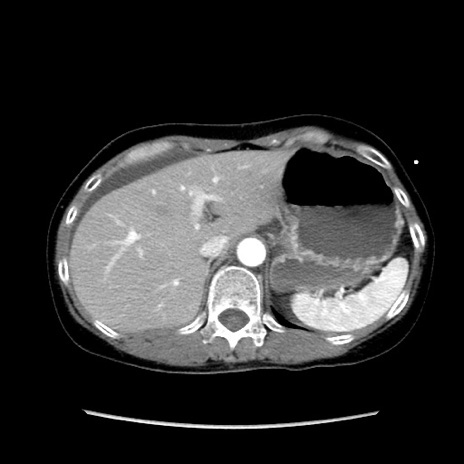

冠状断像

【症例】40歳代 女性

【主訴】上腹部痛、嘔気・嘔吐

【現病歴】約9時間前頃から急に上腹部痛、嘔気、嘔吐が出現。改善しないため救急要請。

【既往歴】子宮頚癌(広汎子宮全摘術、放射線療法)、腸閉塞

【身体所見】腹部:平坦、軟、腸雑音亢進、上腹部を中心に腹部全体に圧痛あり。

【データ】WBC 8400、CRP 0.03